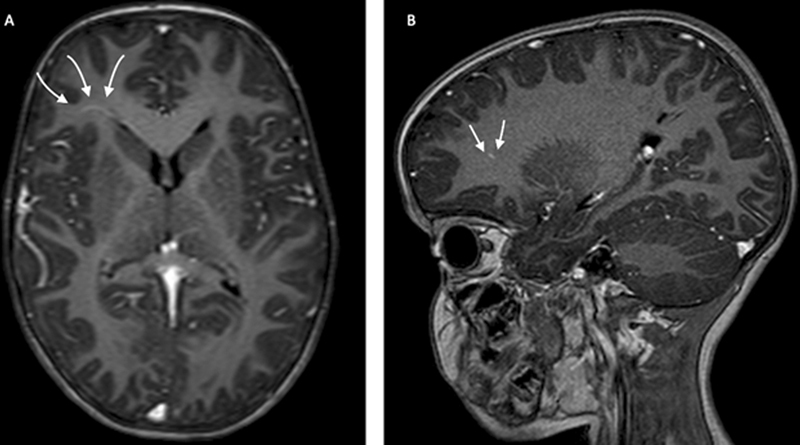

Abstract Image